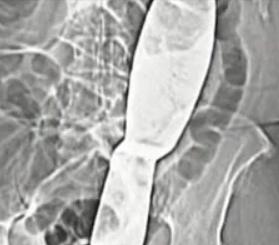

Češki kirurzi iz bolnice u gradu Ivancice suspendirani su nakon što je otkriveno da su u tijelu pacijentice nakon operacije zaboravili 30 centimetara dugačku lopaticu.

Kirurški instrument pronađen je tek pet mjeseci nakon što se nevjerojatna pogreška dogodila, a zbog užasnih bolova 66-godišnja pacijentica pomišljala je i na samoubojstvo.